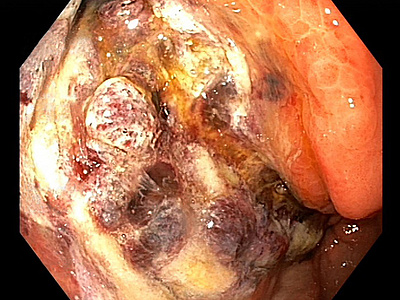

A 41-year-old female with ocular malignant melanoma, metastatic to both lobes of the liver, presented with nausea, vomiting and epigastric pain. Upon endoscopy, a large ulcerated lesion, extending from the corpus to the duodenal bulb, was detected (Panel A). Upon histology, ballooning cells with mild to moderate nuclear atypia were observed within the surface and foveolar epithelium (Panel B-C). Marked nuclear pleomorphism, hyperchromasia and loss of polarity, along with increased cytoplasmic eosinophilia were present within the deep gastric glands (Panel D). Mitotic figures were not seen, and  the  Ki-67 labelling index was low (Panel E). p53 overexpression was noted in the atypical cells, however with  heterogeneous staining, thereby indicating an activated wild-type pattern (Panel F).

Metastatis to the liver may be managed by local ablative therapies such as transarterial chemoembolization (TACE). Fotemustine is a nitrosourea alkylating agent that is used to treat metastatic melanoma. Gastroduodenal ulcers are a rare complication of TACE, which may be explained by the shared origin of hepatic and gastroduodenal arteries.